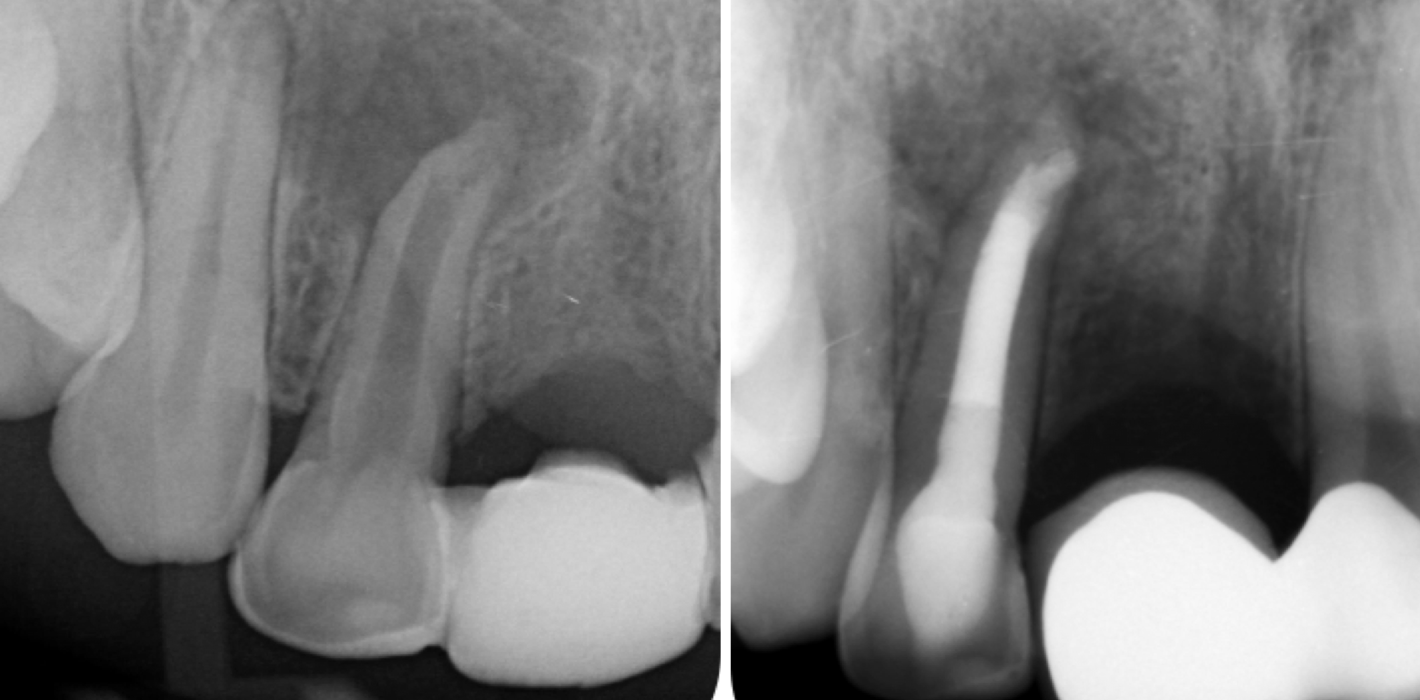

Zwei Monate später konnte die definitive Obturation erfolgen. Da der Kanal nun trocken war, konnte die Dentinbrücke im apikalen Bereich unter Sicht entfernt werden (Abb. 3). Das Mineral Trioxid Aggregat (MTA, Medcem) wurde frisch mit steriler Kochsalzlösung angemischt und mithilfe einer MTA-Gun (MAP-System, Produits Dentaires) sowie individuell angepassten Guttaperchastiften in den gekrümmten Kanalabschnitt eingebracht. Die größte technische Herausforderung bestand im Einbringen eines dichten apikalen MTA-Verschlusses hinter der Kurvatur (Abb. 4). Nachdem dieser Verschluss gesetzt war, wurde der restliche Kanal mit einem Epoxidharz-Sealer (AH Plus, Dentsply Sirona) und erwärmter Guttapercha mittels warm-vertikaler Kompaktion gefüllt und der Zugang adhäsiv verschlossen (Abb. 5).

Kontrollaufnahmen nach drei, sechs, neun, zwölf und 24 Monaten zeigten eine fortschreitende knöcherne Heilung (Abb. 6–10). Die Patientin war beschwerdefrei und zeigte sich mit dem Ergebnis sehr zufrieden. Radiologisch war eine deutliche Rückbildung der Läsion erkennbar, wenngleich eine geringe apikale Aufhellung persistierte. Weitere Verlaufskontrollen wurden empfohlen.